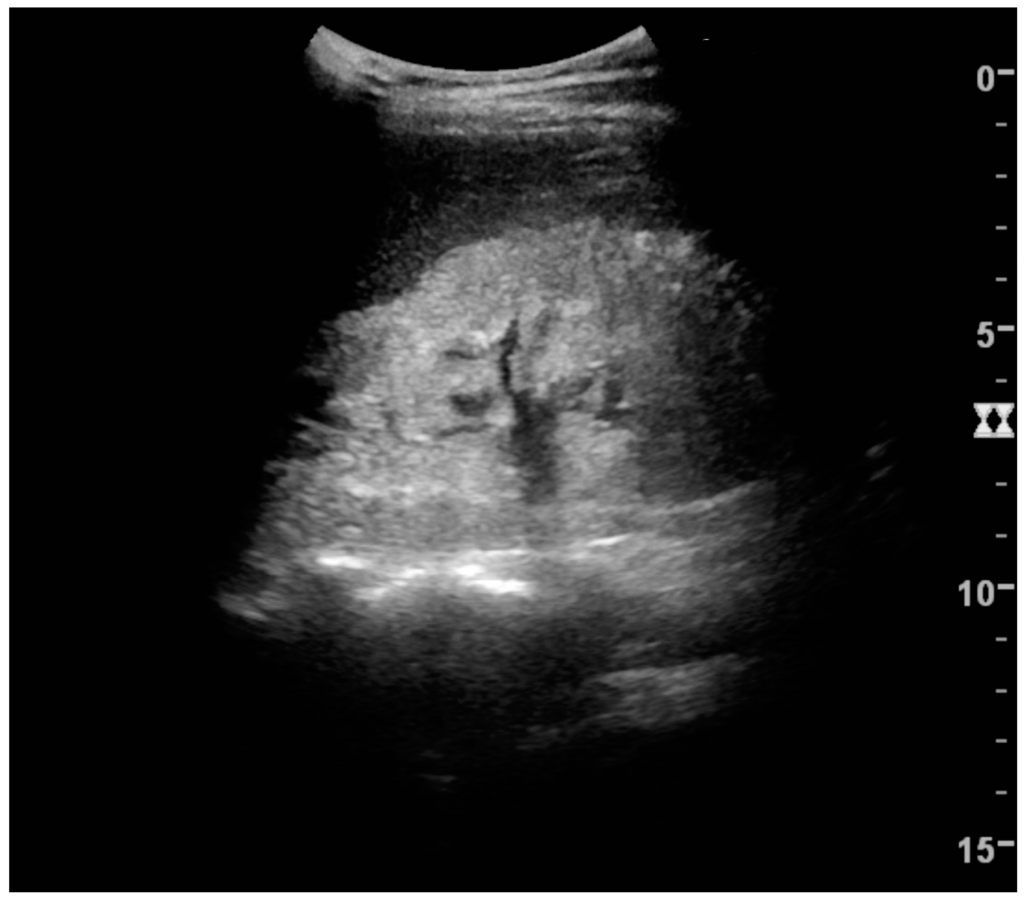

8. Chronic Kidney Disease

US is useful for diagnostic and prognostic purposes in chronic kidney disease. Whether the underlying pathologic change is glomerular sclerosis, tubular atrophy, interstitial fibrosis or inflammation, the result is often increased echogenicity of the cortex. The echogenicity of the kidney should be related to the echogenicity of either the liver or the spleen (Figure 22 and Figure 23) [2]. Moreover, decreased renal size and cortical thinning are also often seen and especially when disease progresses (Figure 24 and Figure 25). However, kidney size correlates to height, and short persons tend to have small kidneys; thus, kidney size as the only parameter is not reliable [2].

Figure 25. End-stage chronic kidney disease with increased echogenicity, homogenous architecture without visible differentiation between parenchyma and renal sinus and reduced kidney size. Measurement of kidney length on the US image is illustrated by ‘+’ and a dashed line.